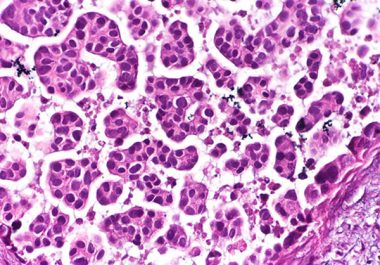

The FDA has approved the FGFR inhibitor erdafitinib for certain patients with urothelial carcinoma The U.S. Food and Drug Administration (FDA) has approved erdafitinib (Balversa) for the treatment of adult patients with locally advanced...